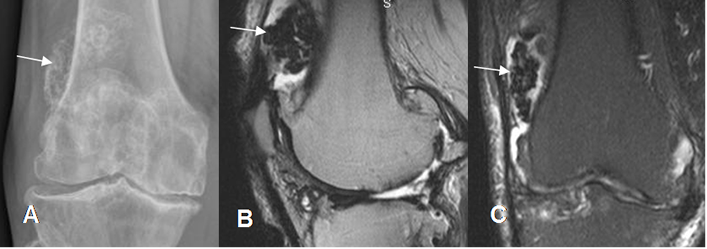

Fig 197. Sinovitis villonodular pigmentaria.

A: Rx lateral. Imagen lobulada y calcificada, en la parte superoexterna de la patela.

B: RM sagital en T2 y C: RM coronal en STIR. Lesión hipointensa en ambas secuencias a nivel intra-articular, que corresponde a sinovitis villonodular pigmentaria.